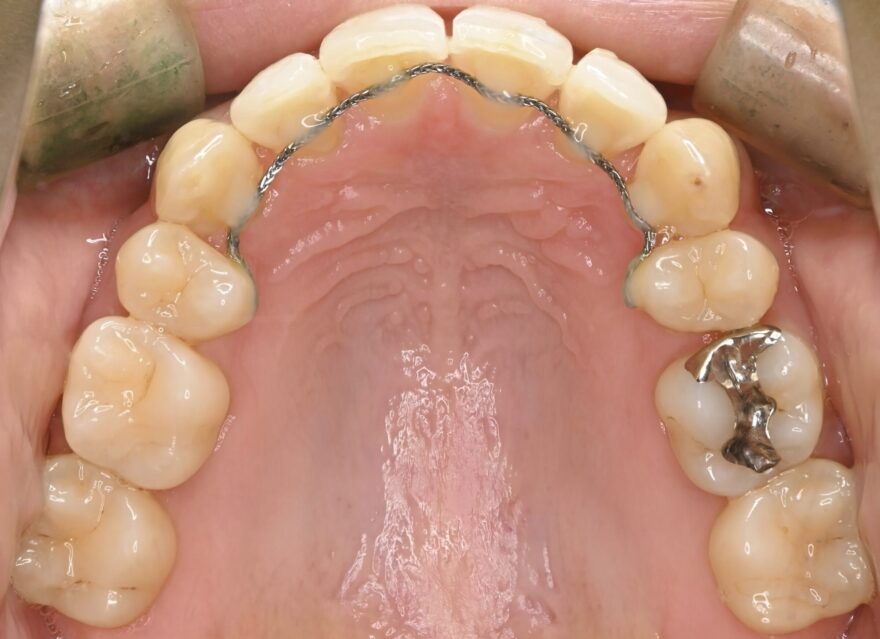

治療後の口腔内写真

約2年の動的期間(歯を動かす時期)で、ここまで美しい歯並びになりました。

ベーシックな表側矯正を選んで頂いても、最終的な仕上がりに差はありません。

前歯のガタガタが無くなりました。

前歯には後戻りを防止するための保定装置が装着されています。